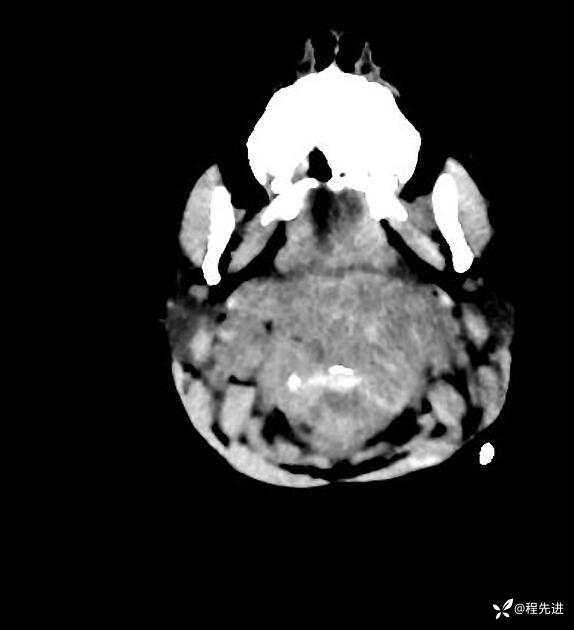

患者性别:男

患者年龄:5岁

简要病史:超速车祸外伤半小时

急诊CT平扫: